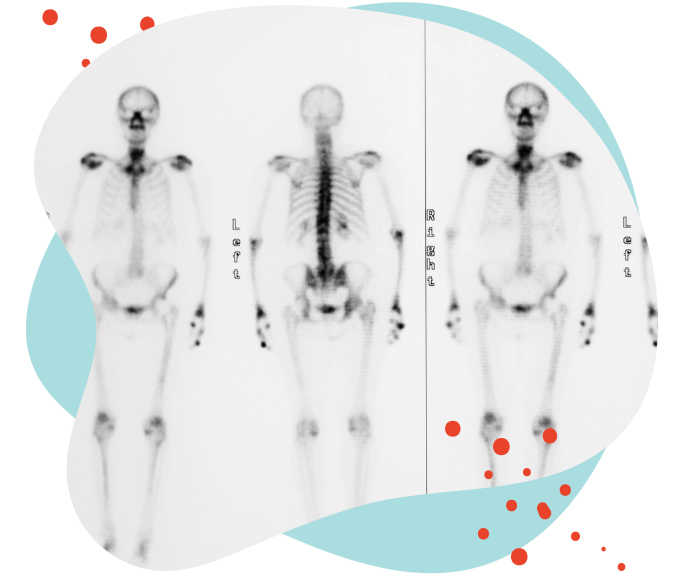

SZINTIGRAFIE – AUF SUCHE NACH METASTASEN

Mithilfe der Szintigrafie können Tumoren oder Metastasen sichtbar gemacht werden.

DURCHFÜHRUNG

Vor der Untersuchung wird Ihnen eine bestimmte, schwach radioaktive Substanz gespritzt, die sich besonders gut in den Knochen verteilt. Bis das geschieht, müssen Sie etwa zwei bis fünf Stunden warten. Danach werden mit einer speziellen Kamera Aufnahmen des gesamten Skeletts gemacht. Dieser Vorgang dauert ca. eine halbe Stunde.

EINSATZ

Die Szintigrafie eignet sich besonders gut, wenn eventuell vorhandene Knochenmetastasen aufgespürt werden sollen. Sie wird aber auch eingesetzt, um zu überprüfen, ob die Brustkrebszellen eventuell in den/die Wächterlymphknoten gestreut haben. Die Ergebnisse dieser Untersuchung dienen der Behandlungsplanung. Im weiteren Verlauf kann sie auch zur Überprüfung des Behandlungserfolges eingesetzt werden.

STRAHLENBELASTUNG

Da nur sehr geringe Mengen an radioaktiver Substanz für die Szintigrafie eingesetzt werden und diese schnell im Körper zerfallen und ausgeschieden werden, ist die Strahlenbelastung eher gering.